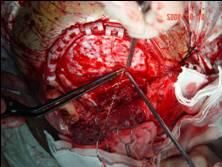

對早期聲門癌,放療或聲帶切除術可獲85%~95%的5年生存率.對早期聲帶癌常選擇放療,因為其後果常能保持正常發音.侵犯前連合的晚期癌,損害了聲帶的活動,侵害了甲狀軟骨或向聲門下擴展,需手術切除.當病變局限於一側聲帶時,常有可能作保留喉發音和括約肌功能的半喉切除術.更晚期的聲門癌需行全喉切除術.早期的聲門上癌對放療有效,但較晚期的聲門上癌而未累及真聲帶者,可作聲門上部分喉切除術以保留髮音和聲門括約肌.如真聲帶受累,需行全喉切除術.早期下咽癌可作擴大的部分喉切除術,較晚期的病變需要全喉切除術.在晚期的聲門上癌和下咽癌,聯合放療和手術治療比單純手術療法更有成效.環狀軟骨後部癌,需要全喉咽切除術,並用游離的空腸瓣和在顯微血管吻合技術下,作下咽腔及頸段食道的再造.對頸部淋巴結轉移者,除喉部手術外,還應聯合套用頸部廓清術或改良廓清術.疣癌則宜手術切除.